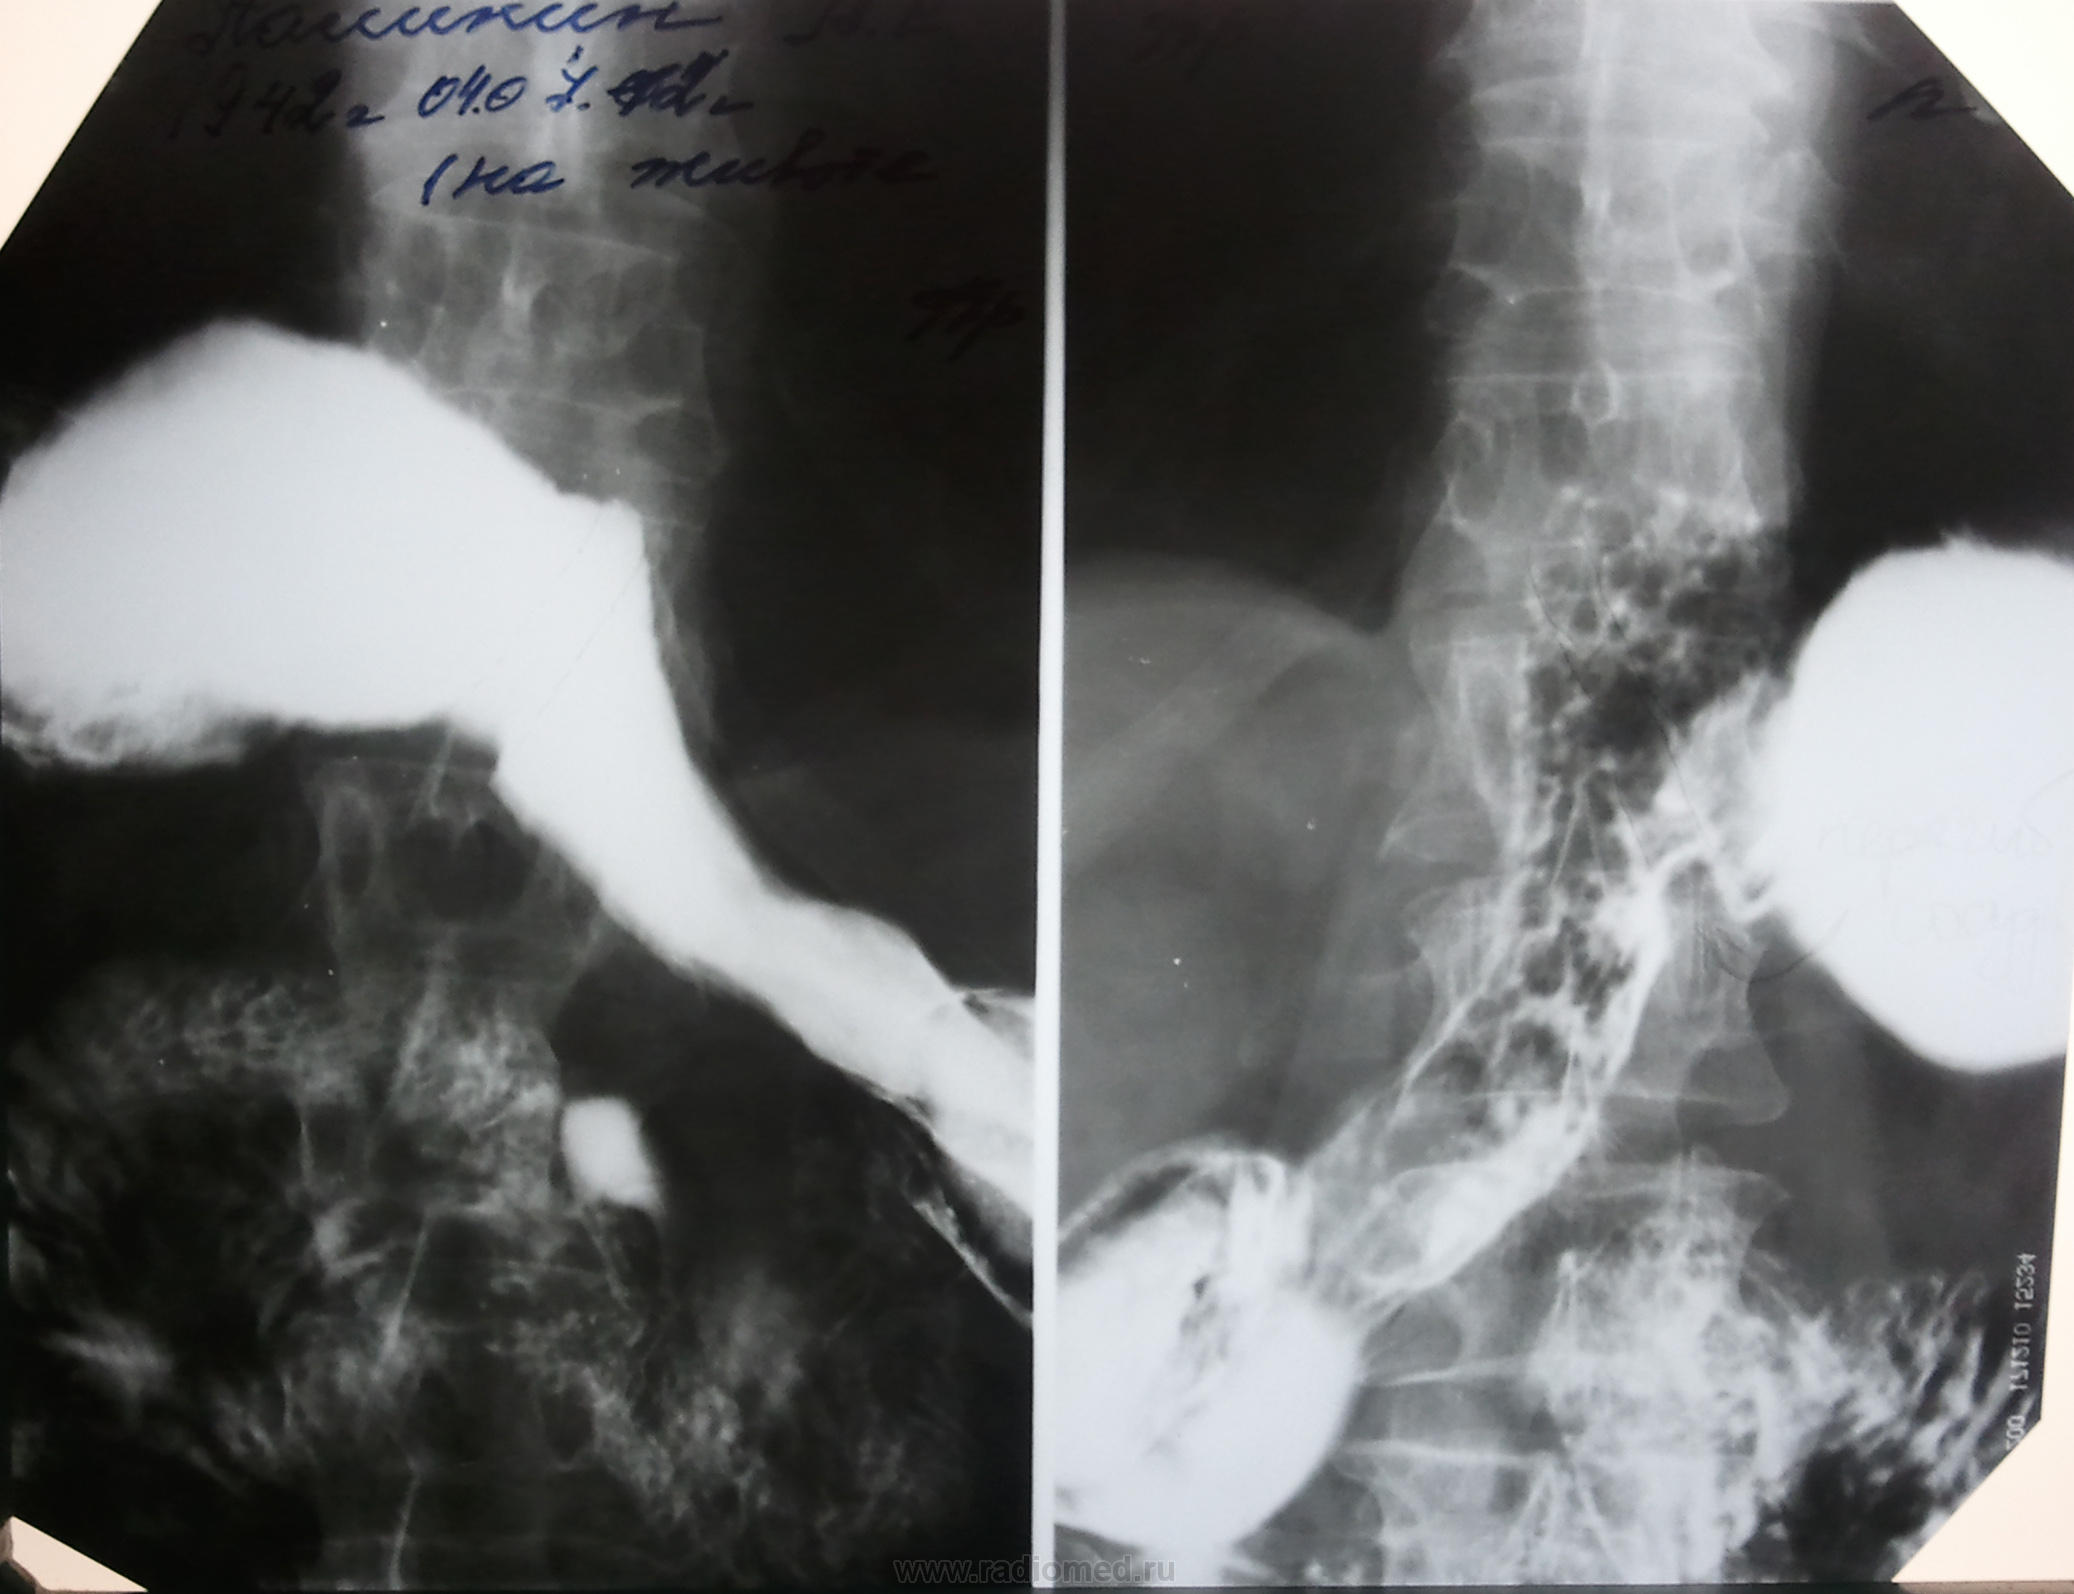

пациент в-общем то без жалоб особых. на скопии определяется сдавление желудка извне каким-то сосудом я так понимаю. но нет здравых идей что это может быть за сосуд..

на снимке я карандашиком подчеркнул для наглядности + стрелка..

Циркулярная ригидность стенок тела желудка, изменение.рельефа. Это, все-таки, больше на рак похоже, а не на сдавление сосудом. По крайней мере, по этим снимкам.

спасибо, Коллеги за комментарии. Конечно, первое что пришло в голову это рак, но очень смутила его идеальная "параллельность". В то же время, изучив Синельникова никаких сосудов которые потенциально могут так сдавить желудок спереди я не нашел. Из крупных сосудов там может быть только селезеночные.. но они идут глубже.

Тоже считаю, что ни о каком сосуде тут речь не идет.

+1 касаемо РИГИДНОСТИ стенок желудка.

+1 за рак тела.